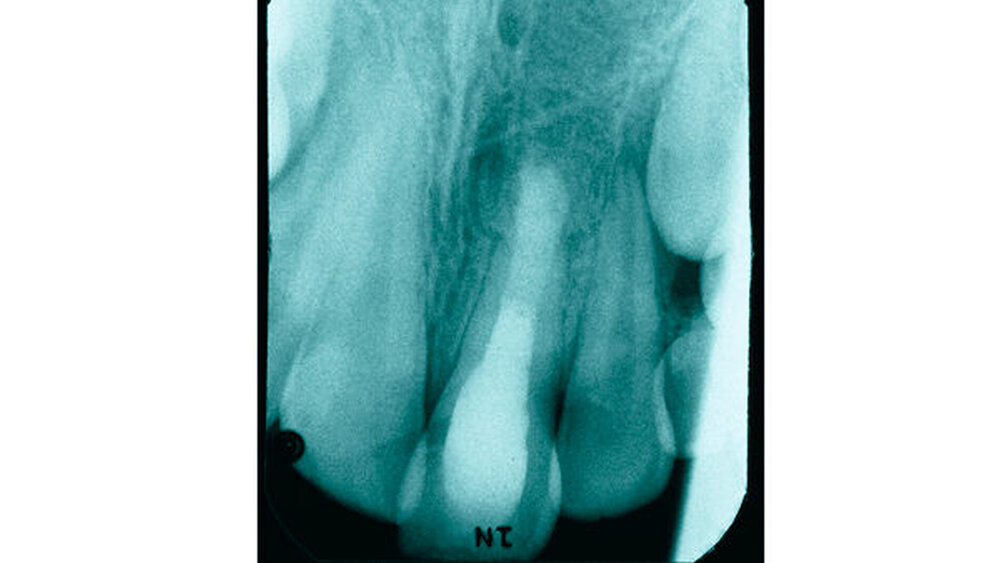

Anamnese: Im vorliegenden Fall war es bei dem zum Unfallzeitpunkt neunjährigen männlichen Patienten bei einem Fahrradsturz zu einem Frontzahntrauma gekommen. Der Junge erlitt bei dem Unfall eine Subluxation am Zahn 21. Weitere Verletzungen waren nicht vorhanden. Da sich der Unfall während eines Urlaubsaufenthalts ereignet hatte, erfolgte die Erstversorgung durch einen Zahnarzt vor Ort. Der gesunde Patient wies zu diesem Zeitpunkt ein altersentsprechendes Wechselgebiss auf. Im Zusammenhang mit der Erstversorgung wurde ein Zahnfilm (Abbildung 1) angefertigt.

Fokussiert auf den betroffenen Zahn 21 zeigte dieser ein nicht abgeschlossenes Wurzelwachstum und ließ eine unfallbedingte Schmelzabsplitterung an der Inzisalkante erkennen. Eine Wurzelfraktur am betroffenen Zahn sowie eine Alveolarknochenfraktur ließen sich auf der angefertigten Aufnahme nicht vermuten.